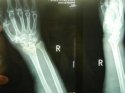

上一期我们讲诉了患桡骨远端骨折的原因及其注意事项, 骨密度仪品牌 国康继续为您讲述桡骨骨折后如何更好的恢复。 1、俗话说伤筋动骨一百天,有钢板的在1年内每月到医院复

桡骨是人体前臂双骨之一,位于前臂外侧,大拇指一侧,分为一体和两端。是前臂长骨之一;蛙、蟾蜍等动物的桡骨与尺骨愈合成桡尺骨。 骨密度仪厂家 国康为您讲述桡骨引起的